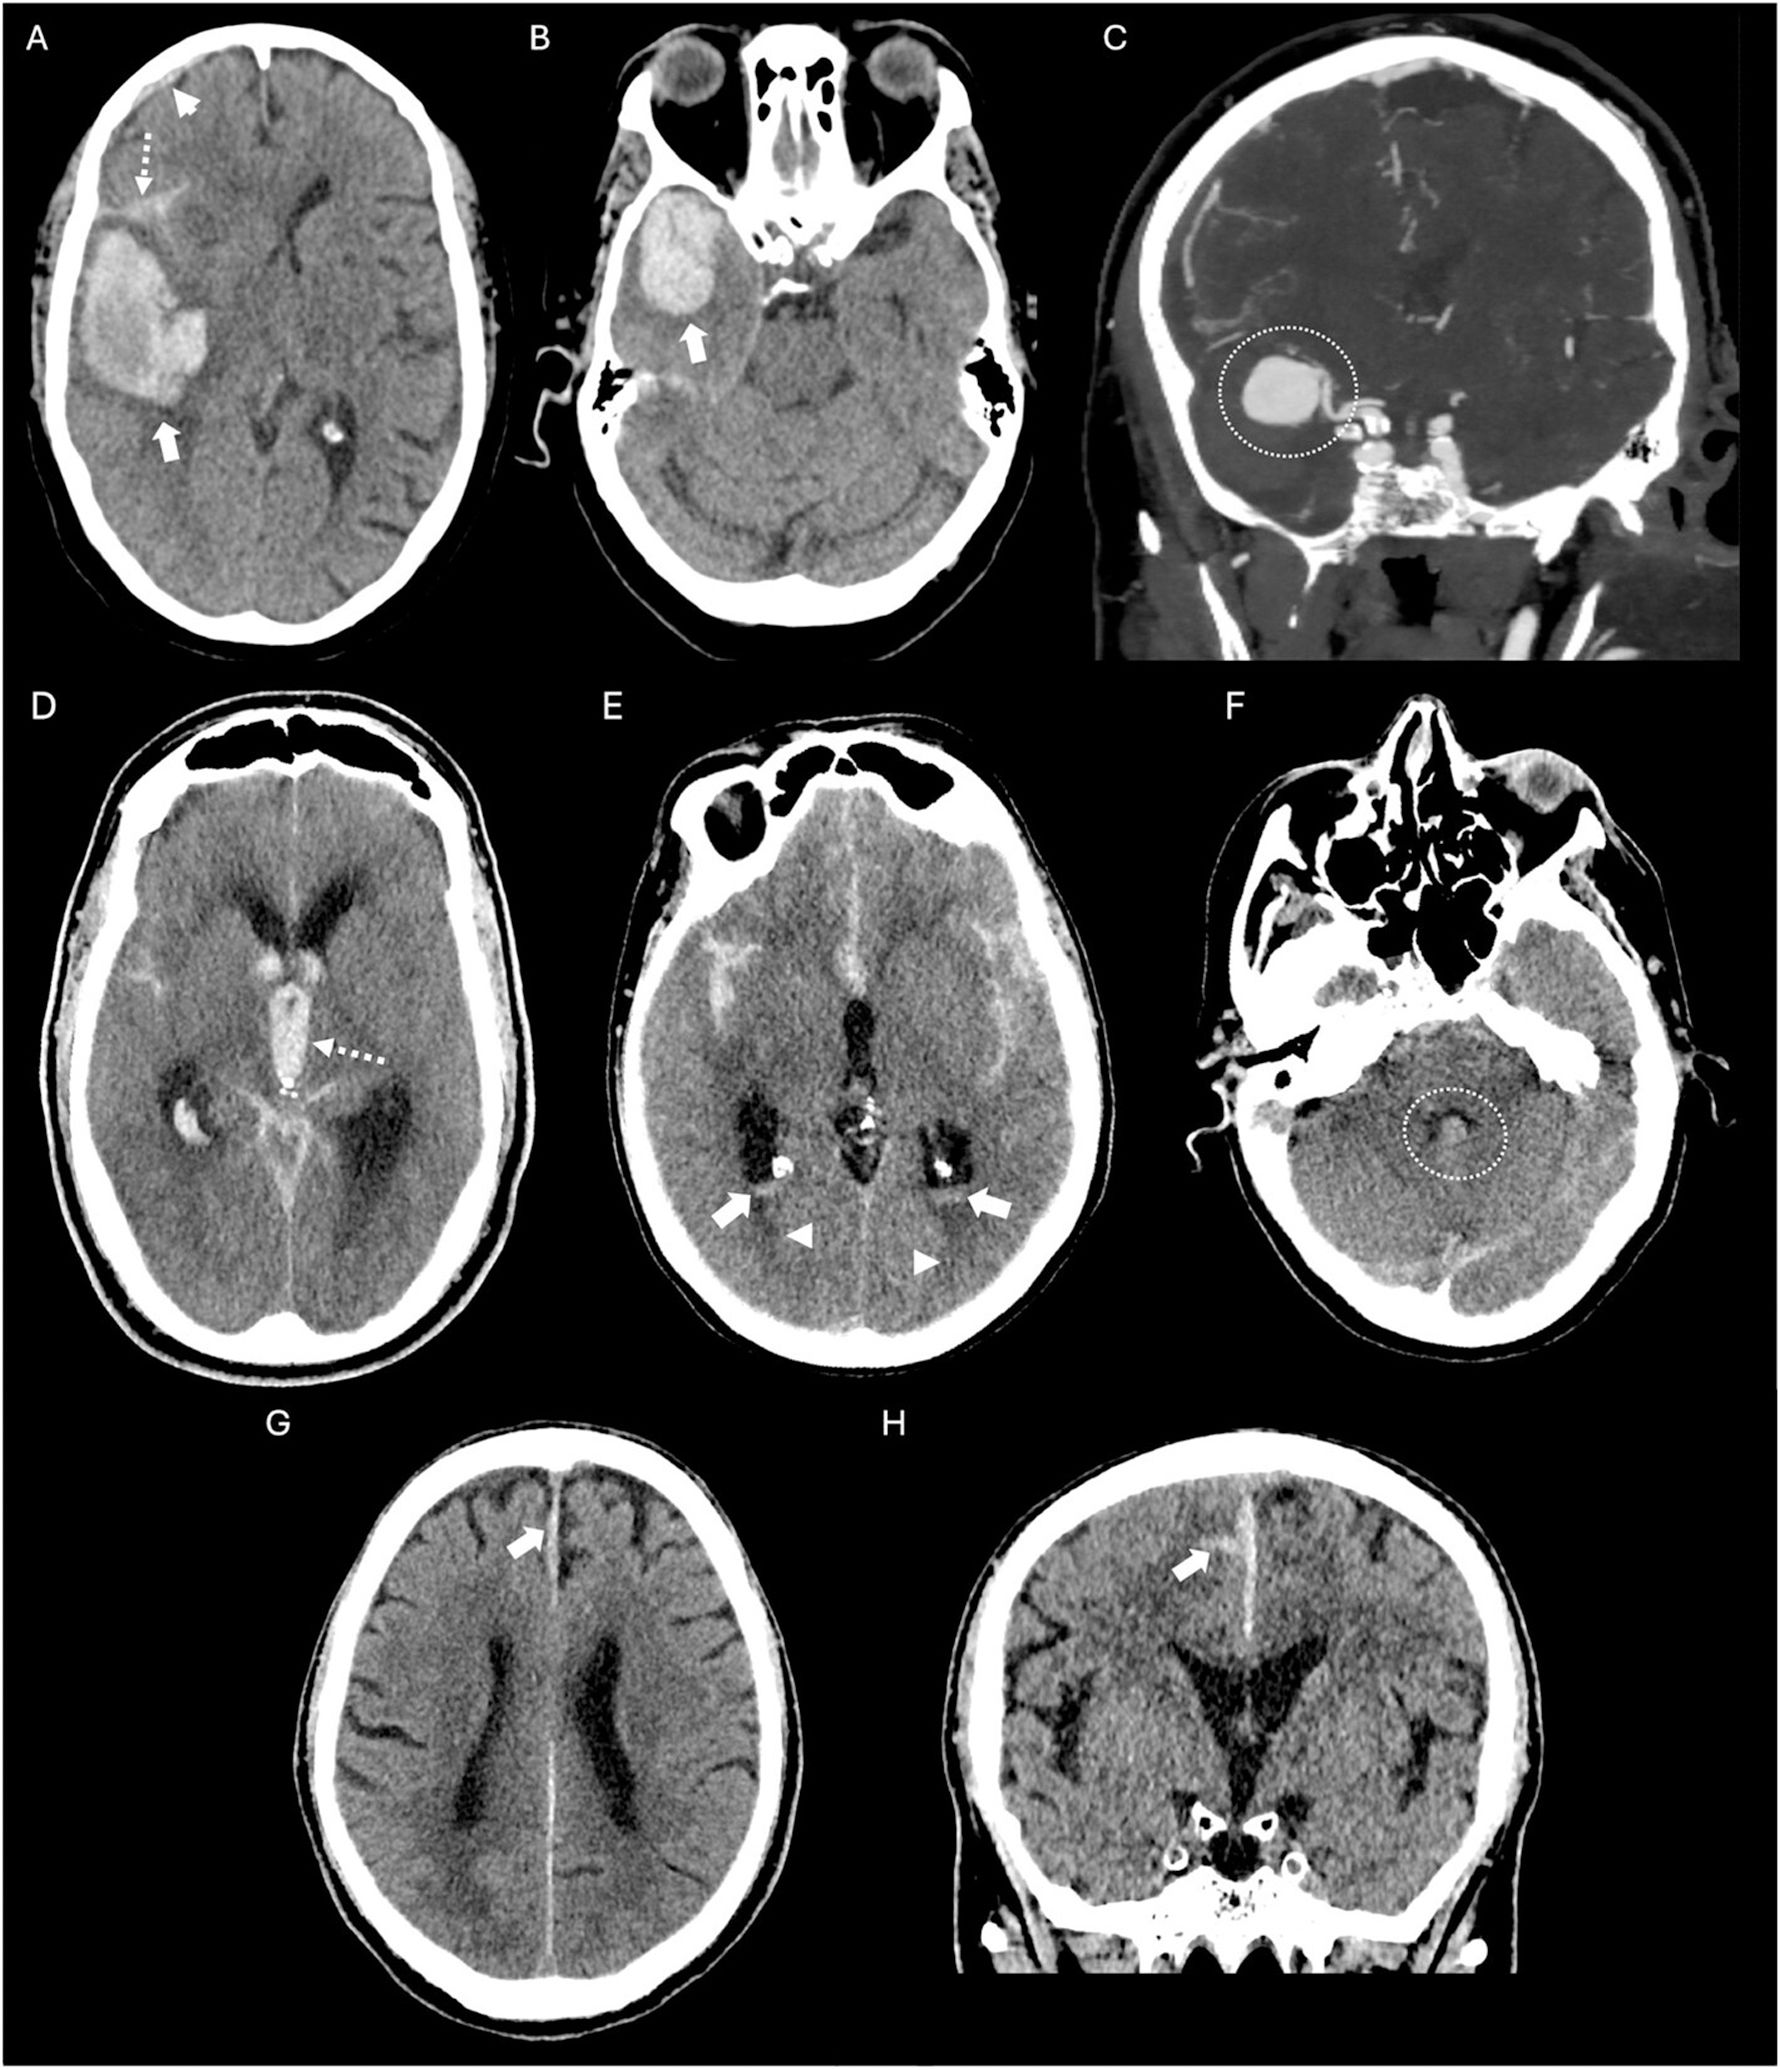

La hemorragia subaracnoidea espontánea (HSA) es una urgencia neurológica que afecta predominantemente a adultos jóvenes, con una elevada tasa de mortalidad y secuelas neurológicas graves en los supervivientes. Su manifestación clínica más característica es la cefalea súbita en trueno, considerada la peor cefalea de la vida, frecuentemente acompañada de alteraciones del nivel de conciencia y rigidez de nuca. La tomografía computarizada craneal sin contraste (TCCSC) constituye la herramienta diagnóstica inicial de elección, con alta sensibilidad. El reconocimiento de patrones de distribución del sangrado en la TCCSC permite orientar el diagnóstico etiológico y valorar la presencia de complicaciones como hidrocefalia, hemorragia intraventricular o edema cerebral. Esta primera parte del artículo proporciona una guía práctica y detallada basada en la imagen para el radiólogo en la fase hiperaguda de la HSA espontánea, diferenciando entre patrones aneurismáticos, perimesencefálicos y corticales, y discutiendo sus implicaciones clínicas, diagnósticas y terapéuticas.

Spontaneous subarachnoid haemorrhage (SAH) is a neurological emergency that predominantly affects young adults, with a high mortality rate and severe neurological sequelae in survivors. Its most characteristic clinical manifestation is a sudden thunderclap headache, often described as the worst headache of one's life, and frequently accompanied by altered levels of consciousness and neck stiffness. Non-contrast cranial computed tomography (NCCT) is the initial diagnostic tool of choice due to its high sensitivity. Recognising the distribution patterns of haemorrhage on NCCT helps guide the aetiological diagnosis and assess the presence of complications such as hydrocephalus, intraventricular haemorrhage or cerebral oedema. This article offers a practical and detailed imaging-based guide for radiologists in the hyperacute phase of spontaneous SAH, distinguishing between aneurysmal, perimesencephalic and cortical patterns, and discusses their clinical, diagnostic and therapeutic implications.